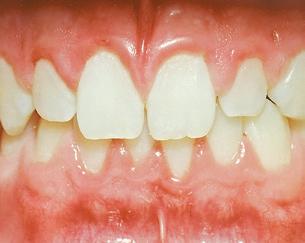

THE PERIO-ORTHO SYSTEMIC LINK

The perio-ortho systemic link has been clearly connected through the years.

As

healthcare providers, we should focus on both disease prevention and treatment modalities when dealing with periodontal disease.

It is now clear that orthodontic health is vital for periodontal and systemic health. Therefore, orthodontic treatment should be one of the treatment options considered in prevention plans, as well as restorative plans in dentistry. Evidence based dentistry has shown that more than just three millimeters of crowding can be a host factor for periodontal disease. Therefore, preventative treatment to avoid periodontal issues should consist of placing the teeth in proper alignment, including reduction or elimination of crowding. Research has also shown that there is significantly greater plaque accumulation in crowded areas. Interestingly, research also indicates that the bacteria present in crowded areas consistently represents more species of periodontopathogens than bacteria from non-crowded regions. The pathogens are more virulent in the areas that are more crowded because they become anaerobic, meaning they grow in the absence of oxygen. As plaque accumulation increases subgingivally, or beneath the gums, the amount of periodontopathogens increases. 2

If we can reduce crowding, then we can reduce aggressive periodontal pathogenic bacteria, which can subsequently decrease the risk of periodontal disease as well as the inflammatory disease processes in the rest of the body. Our currently preferred options for reducing crowding include traditional braces and clear aligner therapy, such as Invisalign®